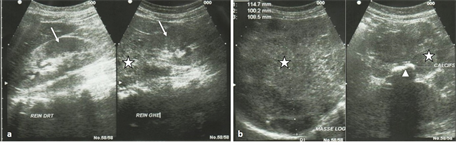

Abdominal ultrasound (Figure 3) revealed a tissue formation developed at the expense of the left adrenal measuring 114 mm × 108 mm × 100 mm, punctuated with calcification in clumps of compatible appearance with AC; kidneys were of normal appearance and there was no live injury.

Figure 3. Phtographs of Abdominal ultrasound. A tissue formation developed at the expense of the left adrenal measuring 114 mm × 108 mm × 100 mm (stars in (a) and (b); punctuated with calcification in clumps (head of arrow in (b) of compatible appearance with AC; kidneys were of normal appearance (arrows in (a)) and there was no liver injury.